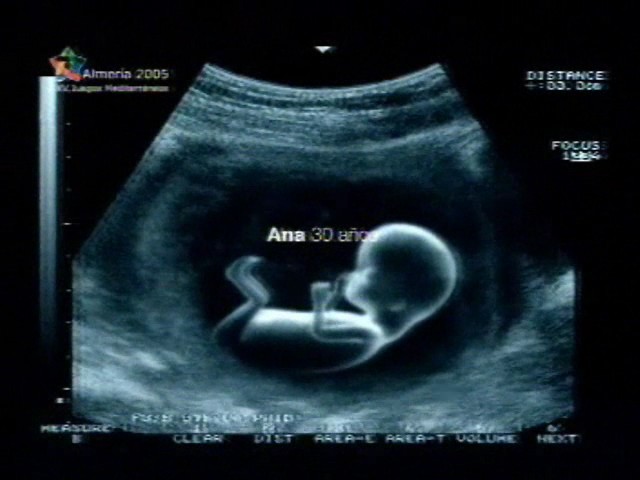

Sin embargo, las estrategias de seducción que hacen uso de los imaginarios sociales no son privativas de las marcas de cosméticos. En un anuncio de la marca de colchones Pikolin6 también se opera ese desplazamiento delirante que ya se daba en el caso anterior. En esta ocasión el spot comienza con una serie de imágenes en las que, sobre fondo negro, podemos leer lo siguiente: Ana, 30 años.

A continuación, sin que de por medio se de ningún otro efecto de transición, aparece la imagen de una ecografía, en plano medio largo, en la que se nos muestra un feto perfectamente formado, con las piernas y los brazos ligeramente doblados, disfrutando de un plácido sueño intrauterino. Resulta remarcable el hecho de que el mensaje que anteriormente aparecía sobre fondo negro queda ahora, tras un breve fundido, en el centro mismo de la pantalla.

Las apelaciones al imaginario del público espectador no pueden ser más evidentes. Mediante el uso de imágenes intercaladas de ecografías, así como de la referencia textual a personajes que en ningún caso aparecen en pantalla pero que se hallan representados por los fetos cómodamente instalados en su lecho intrauterino –recordemos que son Ana y Manuel, de 30 y 40 años, respectivamente –,el emisor de la comunicación visual nos da a entender que los colchones publicitados son, en términos de comodidad, verdaderos sucedáneos del útero materno, y que tan sólo en el interior de éste se podría gozar de un descanso tan cómodo y prolongado. La metáfora delirante, a la que anteriormente hacíamos alusión, se opera aquí de forma verdaderamente inesperada ya que el espectador, ante las imágenes que contempla, no puede hacer otra cosa más que identificarse no sólo con la mujer que se encuentra tumbada en el colchón de la marca publicitada, sino también probablemente con el feto que aparece en las ecografías. Cabe mencionar al respecto que para el psicoanálisis la fuente de la que mana la insatisfacción es precisamente la imposibilidad, inconsciente para el sujeto, de gozar de una completud semejante a esa completud primera de la que participa el feto aún nonato7. En definitiva, el spot parece querer decirnos que en los colchones anunciados nos sentiremos tal y como nos sentíamos en el útero materno, lo cual supone, siguiendo la trama narrativa del anunciante, la expresión pura de la comodidad y el sosiego.

Los registros sonoros del spot refuerzan la trama narrativa anteriormente mencionada. Los lentos acordes de una guitarra acústica acompañan a una voz masculina que canta, en inglés, una lenta canción que parece cumplir las funciones de una “nana”. El ambiente que muestran las imágenes, en su suceder fílmico, es de un sosiego absoluto, aún más teniendo en cuenta el sosiego que deben experimentar los fetos en el interior del útero materno. No hay cabida en la trama para la rapidez y fugacidad habituales en los spot publicitarios. Las imágenes permanecen en pantalla el tiempo suficiente para que el espectador tenga constancia de la envergadura de lo que contemplan sus ojos. Es, en definitiva, el anuncio de un sueño, el sueño que experimentamos en nuestra existencia intrauterina.

Tanto el plano denotativo como la dimensión connotativa del spot, en sus componentes plásticos e icónicos respectivamente, confluyen en una significación de tipo simbólica, esto es, marcadamente abstracta lindante a lo imaginario. Los planos de las ecografías, siempre tomados en una perspectiva lateral y a una distancia suficiente para que se aprecien los fetos en toda su magnitud; los colores claros, predominando los azules y los tonos blanquecinos, sugiriendo del mismo modo la pureza de un sueño sin interrupción ni mácula; los planos de la mujer, cuyos cabellos rubios concuerdan con el tono elegido por la trama narrativa del spot, vestida en color blanco y gris, siempre tenues y difusos. El desplazamiento, conducente a la identificación del espectador con aquello que contemplan sus ojos, es también evidente en este caso, lo que demuestra una vez más la pertinencia del análisis psicosocial del imaginario publicitario en todos los registros del spot televisivo, desde los más simples a los más elaborados. La estrategia de la seducción por medio del desplazamiento hacia el imaginario del espectador no es sólo privativa de un tipo de producto determinado, sino que atañe, cada vez más, a cualquier producto que quiera ser presentado como una apelación simbólica al espectador, esto es, como condensación de su propio imaginario.